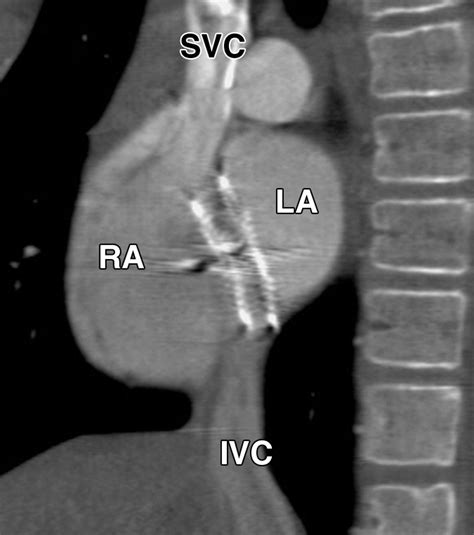

The Amplatzer Septal Occluder is specifically designed to address this by sealing the defect. It is essentially a self-expanding, double-disk device made from a flexible nitinol wire mesh. Once placed, it creates a "sandwich" effect that covers both sides of the hole, allowing the patient's own tissue to grow over the device over time, effectively healing the septal wall.

• Deployment: The Amplatzer Septal Occluder is pushed through the catheter. The left atrial disk is deployed first to anchor the device, followed by the right atrial disk.